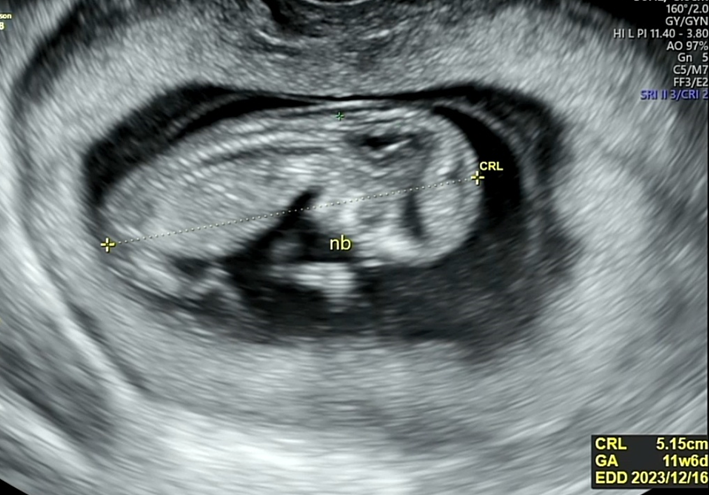

이제 우리 짱튼이가 13주가 되었는데요. 11주차에 난임병원을 졸업하면서 정밀초음파를 한번 보았습니다.

1차 기형아검사 시기는 11주부터 13주 사이에 진행합니다.

정밀초음파를 보면서 전반적인 태아의 성장발달을 관찰하는데요.

아기의 코뼈가 형성이 되었는지, 머리와 장기들이 형성되고 있는 중인지도 살펴봅니다.

코뼈 역시 길이를 재기도 하고요.

검진내용 (정밀초음파)

목투명대가 1mm - 3mm 사이이면 정상이라고 합니다.

3mm가 넘어가면 다운증후군이 의심된다고들 하는데요.